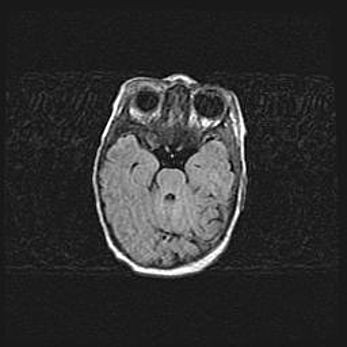

Лейкомаляция с кистозно-глиозной дегенерацией головного мозга.

Возраст: 2 месяца 25 дней

Вес: 6400 г

Окружность головы: 40 см

Срок гестации: 41 неделя

Лейкомаляцию относят к ишемически-гипоксическим повреждениям головного мозга, диагностируемым у новорожденных. При лейкомаляции в головном мозге обнаруживают очаги некроза, возникшие после тяжелой гипоксии и нарушения кровотока. В процессе морфогенеза очаги проходят три стадии: 1) развития некроза, 2) резорбции и 3) формирования глиозного рубца или кисты. Перивентрикулярная лейкомаляция (ПЛ) встречается примерно в 12% случаев среди новорожденных, обычно – у недоношенных детей, причем, частота ее зависит от массы, с которой младенец появился на свет. Наибольшее число малышей страдает лейкомаляцией, если масса при рождении 1500-2500 г.